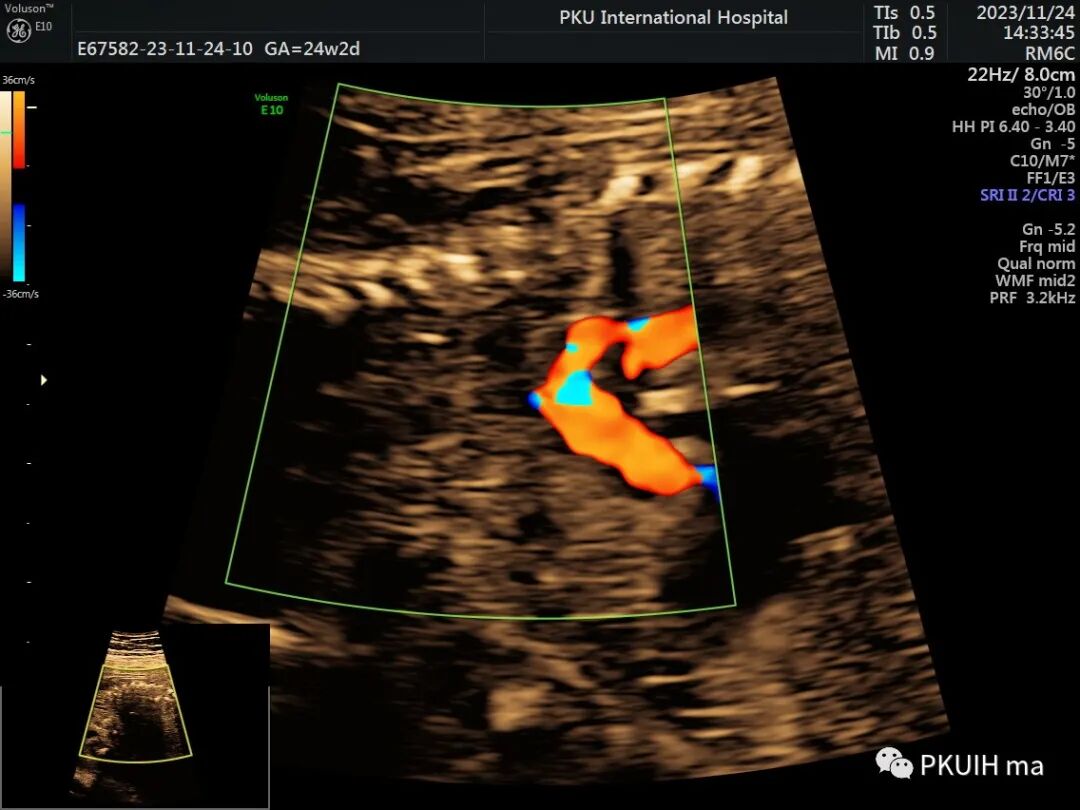

最后可借助于CDFI,CoA胎儿主动脉峡部出现持续性血流信号,当出现湍流时,CoA发生风险明显增加。严重的峡部可出现反向血流灌注。